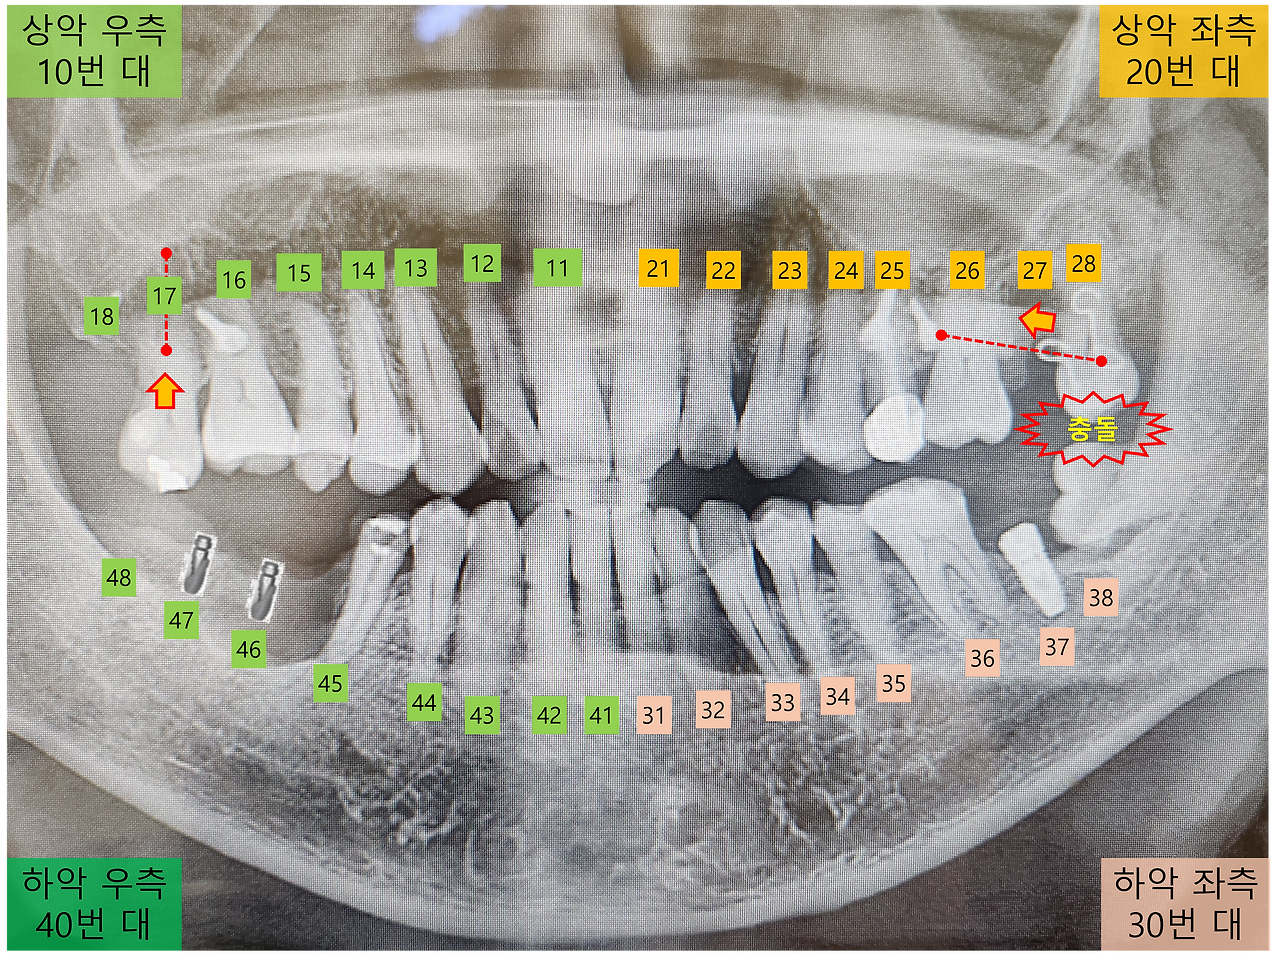

오른쪽 어금니 부위에 임플란트 식립을 위해 46번과 47번 치아를 발치한 이후, 씹는 기능이 저하되어 주로 음식을 먹을 때 왼쪽을 사용하고 있습니다. 그런데 근래에 음식을 씹을 때마다, 교정 중인 왼쪽 28번 치아가 뭔가와 비껴 맞물리는 증상이 있습니다.

교정전문의에게 이런 증상에 대해 설명을 하니, 치아 맞물림 확인을 위해 교합지를 넣은 후 "이로 꽉 물어보세요"하더군요. 확인한 결과는 28번 치아가 교정 과정에서 이동하면서, 옆으로 누워있는 사랑니와 충돌을 하는 것이라고 합니다.

왼쪽 치아 충돌.png [파노라마 사진으로 확인한 치아의 충돌]

예전에는 28번 치아와 사랑니 사이에 간격이 있어 괜찮았는데, 치아가 이동하면서 충돌이 발생한 것이니 교정이 잘 되고 있다고 봐야 할 것 같습니다. 이런 충돌을 해결하기 위해, 28번 치아와 사랑니가 맞닿고 있는 부분을 조금 갈아내는 치료를 했습니다. 치료 후 이를 악물어 보고 좌우로 움직여 보았을 때, 이전의 느꼈던 불쾌한 감각은 완전히 사라졌습니다.

특히 왼쪽 17번 치아는 유실된 아래쪽 48번 치아로 인해, 잇몸에서 많이 내려온 상태입니다. 그래서 17번 치아를 다시 위쪽으로 당겨 올리는 교정 중으로, 치아의 안쪽과 바깥쪽을 고무줄로 연결하여 당기고 있습니다. 크게 불편하거나 아픈 증상은 없는데, 잇몸에 박은 스크루로 인해 입 안쪽이 쓸려 불편하기는 합니다.

오늘은 입술 쪽으로 비스듬하게 나온 17번 치아를 입 안쪽으로 넣는 시술을 하기로 했습니다. 이를 위해서 17번 치아의 안쪽은 계속 고무줄로 잡아당기고, 치아의 바깥쪽은 철사로 잡아주어 유지만 하는 방식으로 진행된다고 합니다.